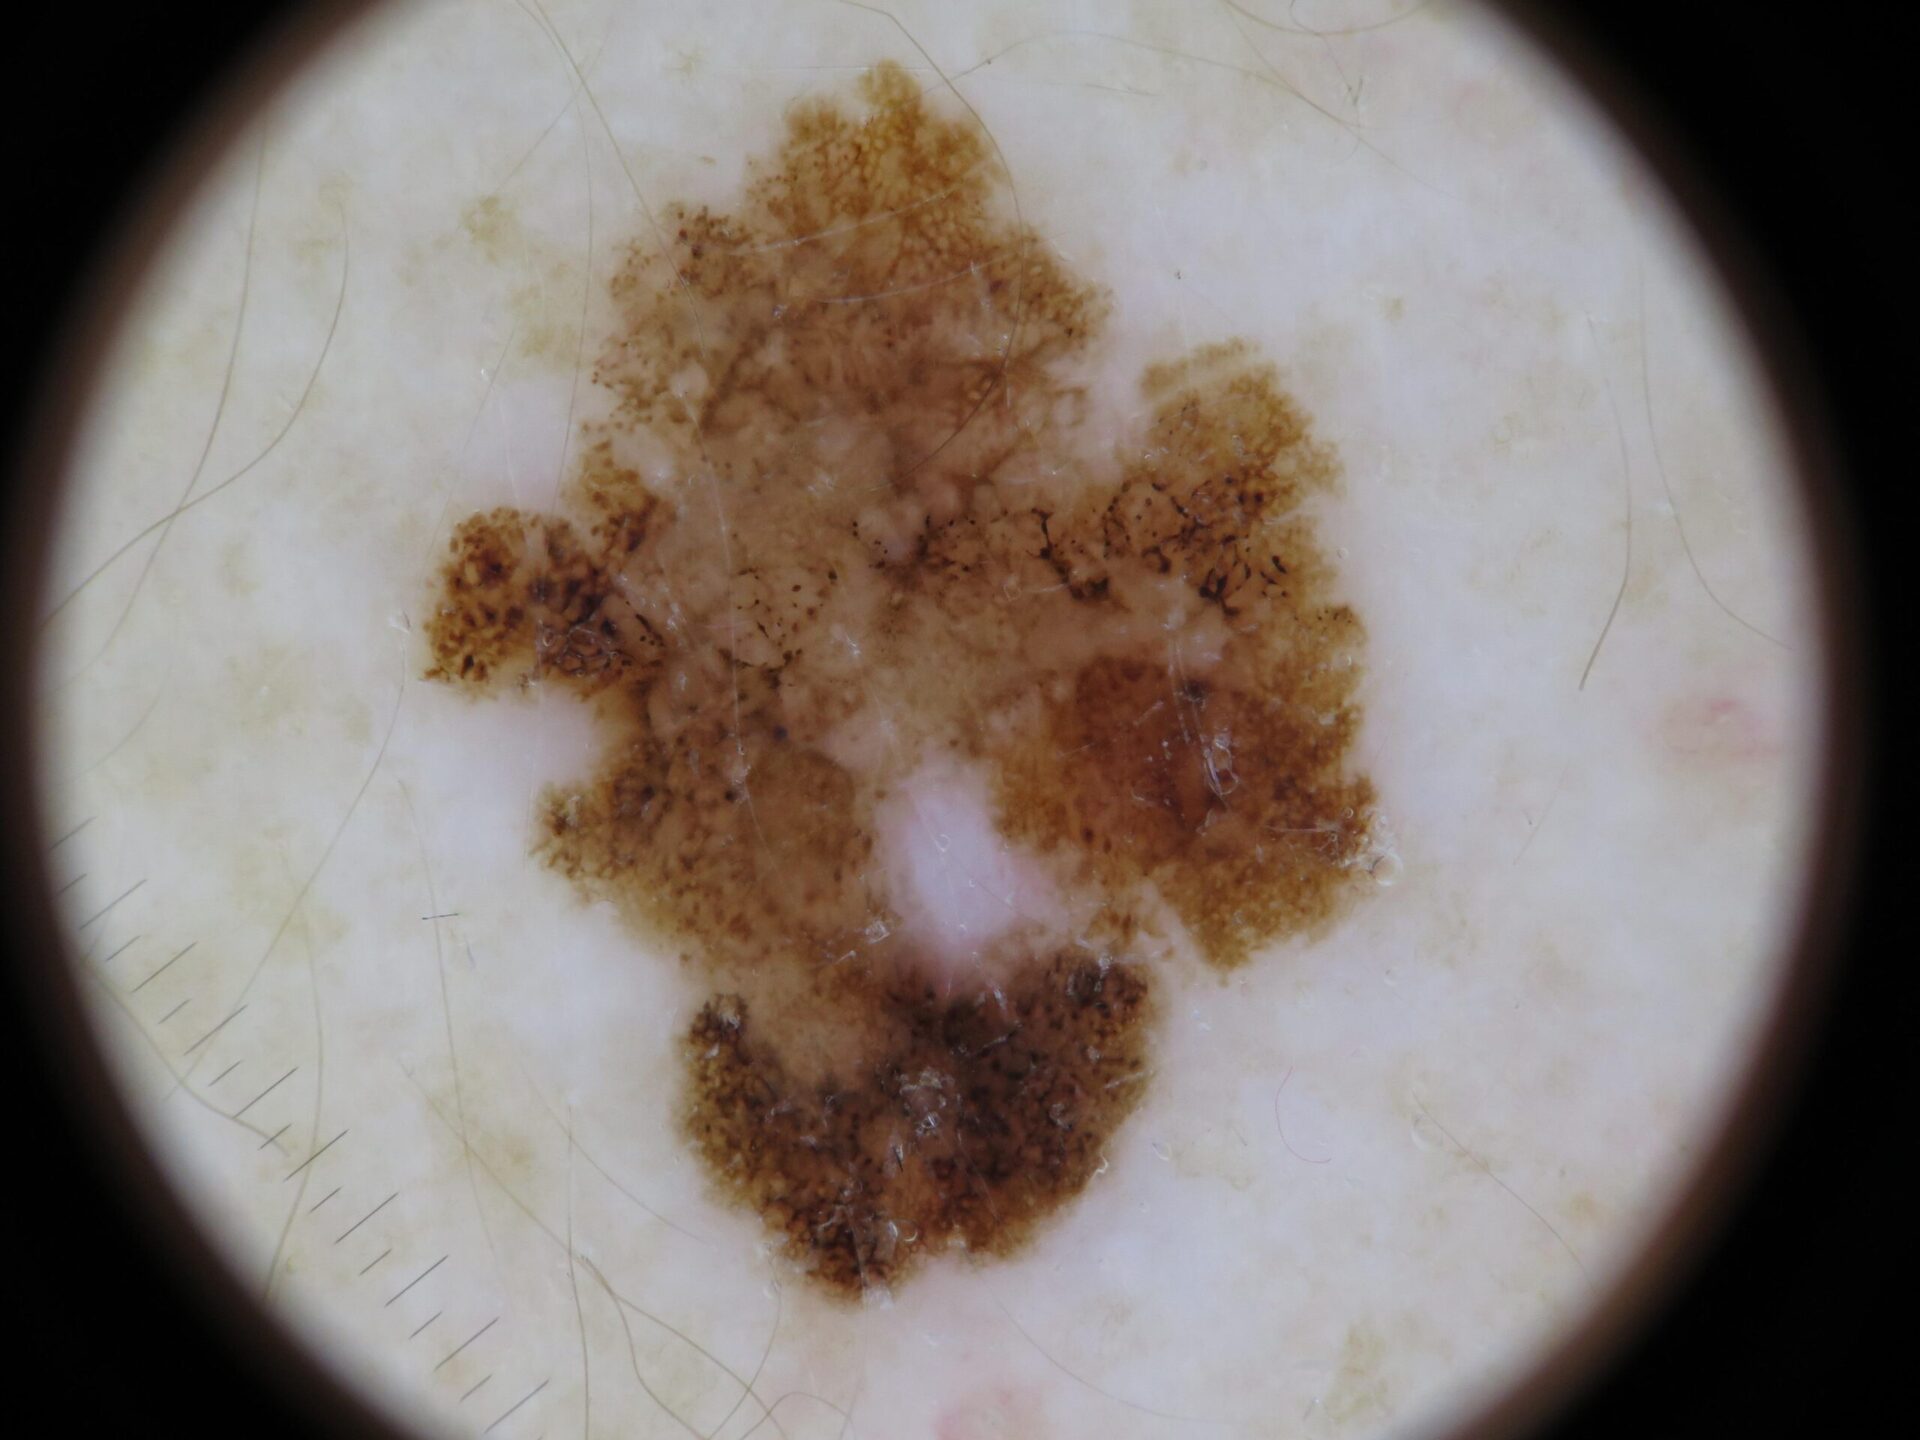

Actinic Keratosis (AK) Photos

Actinic keratosis on head or neck. Photo: International Skin Imaging Collaboration at isic-archive.com

Actinic keratosis on posterior torso. Photo: International Skin Imaging Collaboration at isic-archive.com